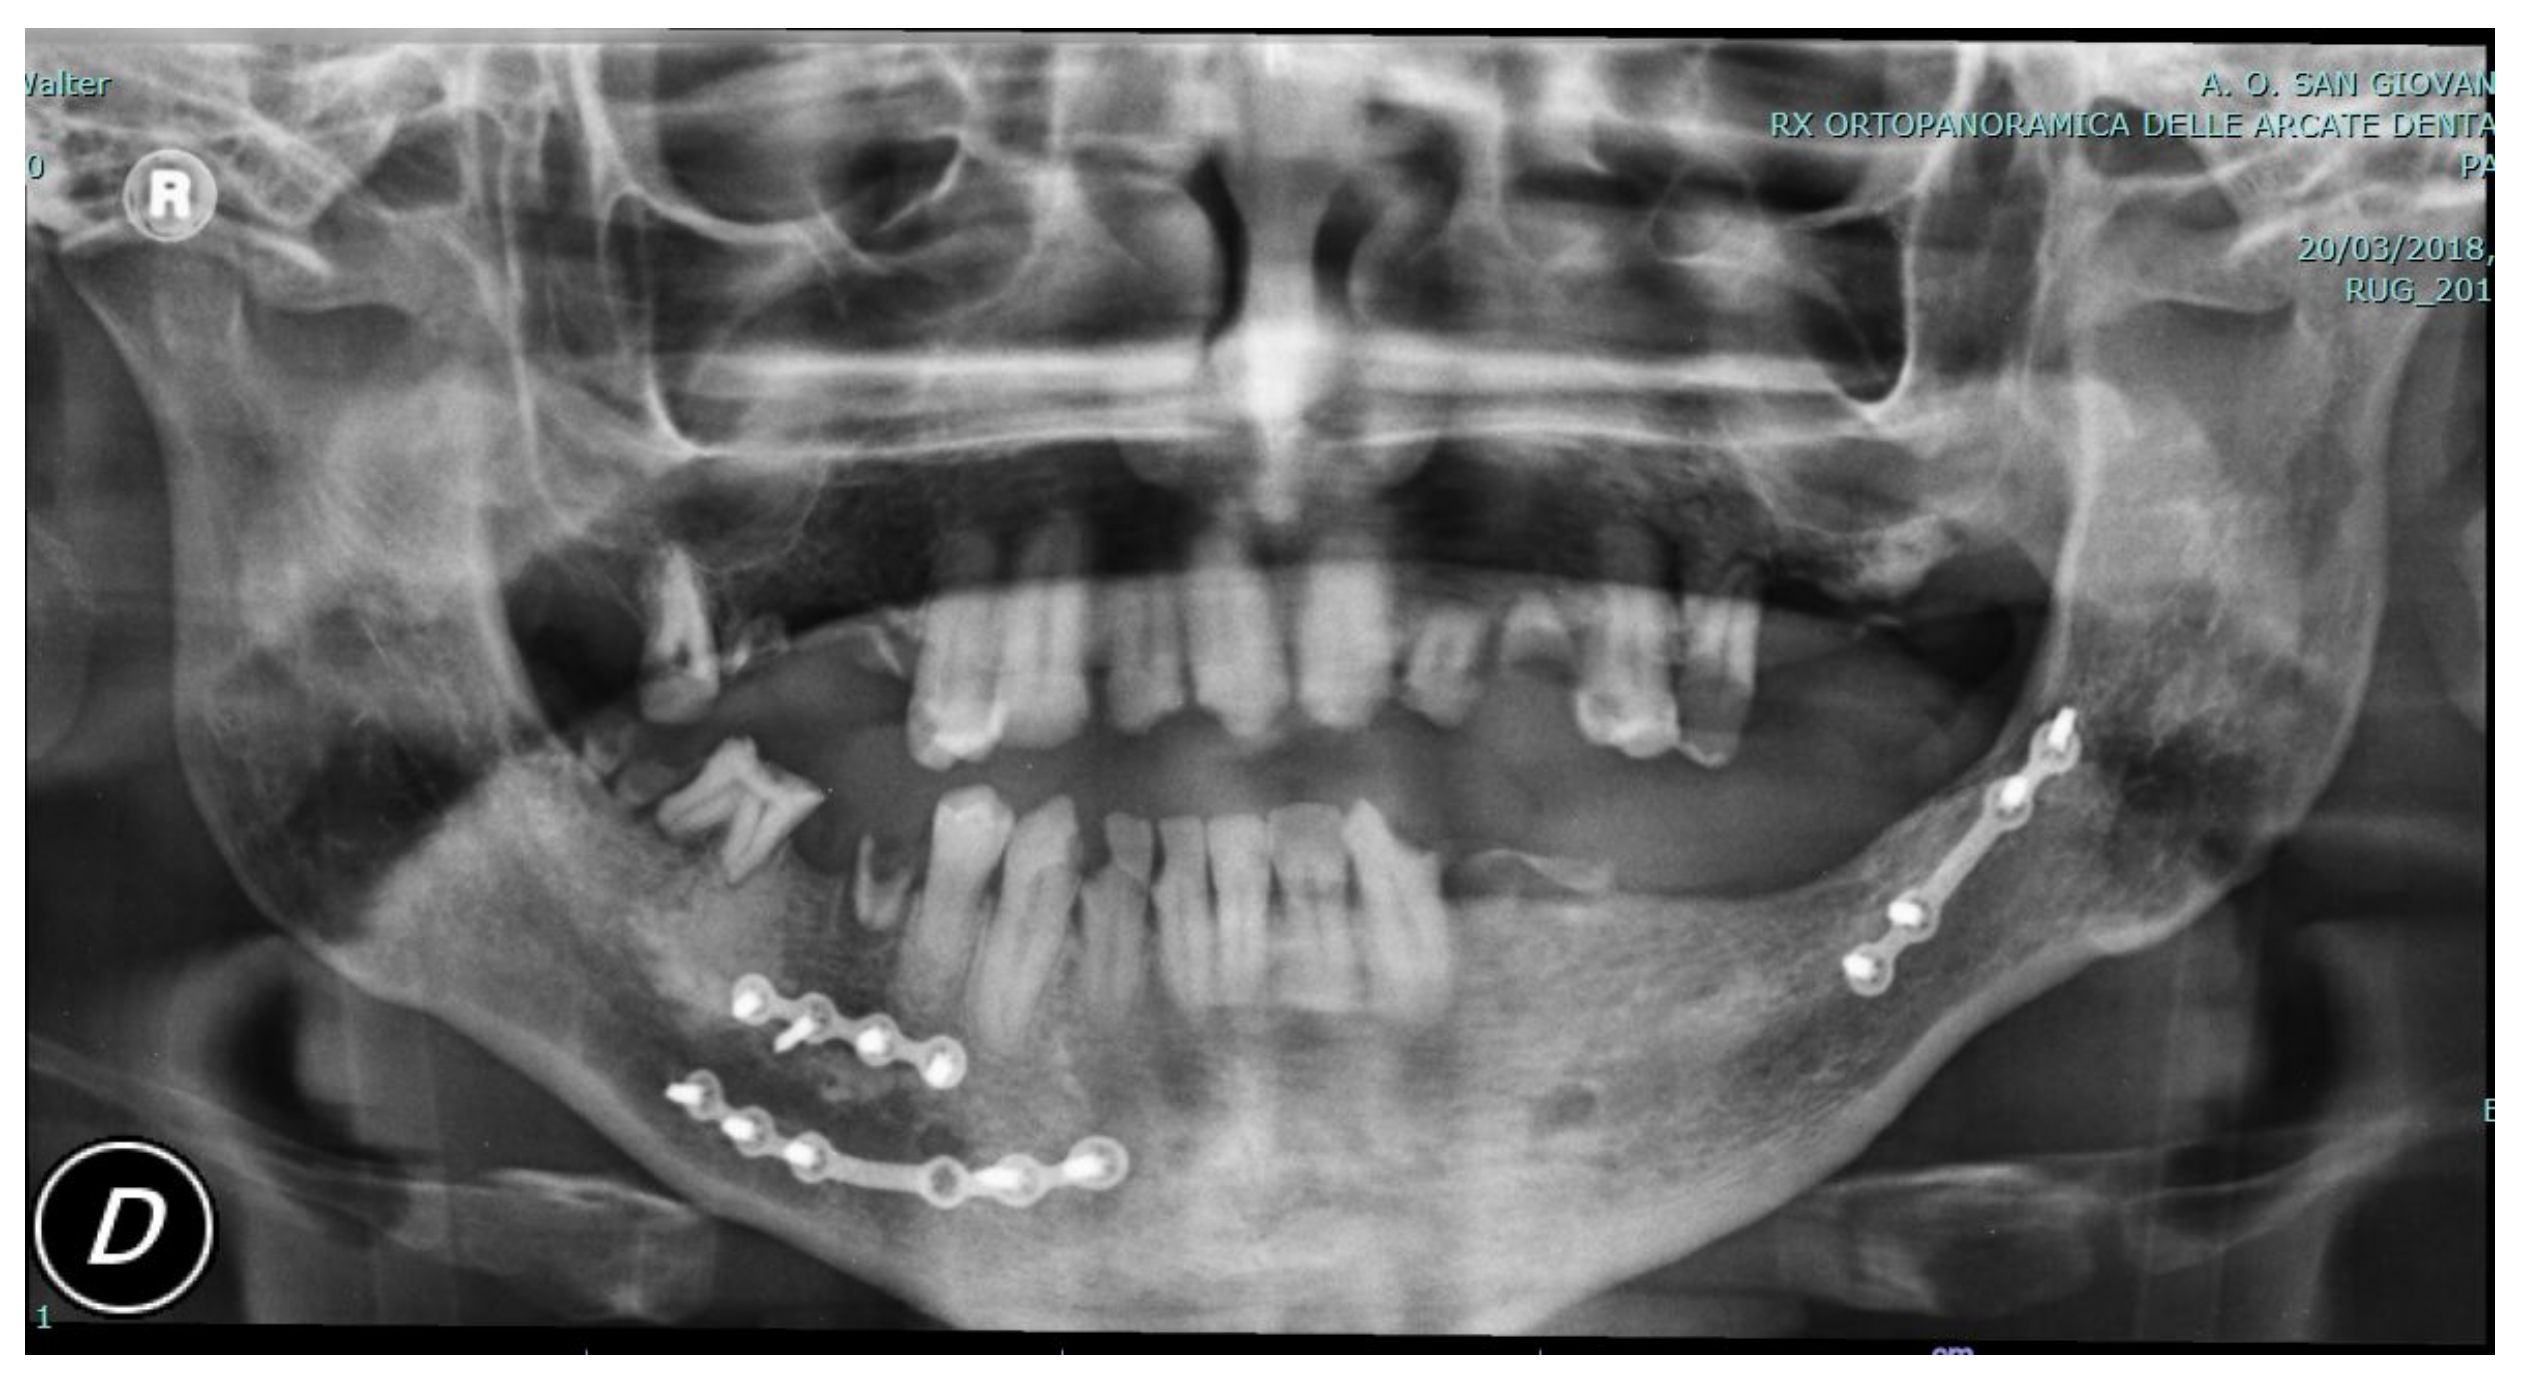

The procedure was adopted in one clinical case on a patient affected by a class III malocclusion with an associated open bite and right deviation of the mandible. The patient was a 27-year-old male already operated on 5 years prior for multiple fractures of the jaw after a car accident. Screws and plates from the previous operation were removed before new orthognathic surgery. Following our procedure, a high-definition skull CT scan was acquired and digital planning was performed. Evaluation of proper maxillary and mandibular segmentation and movements was performed considering class III, open bite, and asymmetry correction. Additionally, evaluation of gap or overlapping of the bone fragments at the osteotomy sites was acquired up to a final bone fragments positioning feasible in relation to anatomic and surgical technique limits. CAD/AM (Computer-Aided Design/Computer-Aided Manufacturing) surgical guides and custom-made fixation plates were acquired before surgery. In this special case, the standard plates were unable to be used for the particular conformation of the bones.

In the following figures, the medical images, orthopanoramic images (Figure 6 and Figure 7) before and after an orthognathic surgery, the implanting screws (Figure 8), and a digital reconstruction (Figure 9) are shown.

Figure 6. Pre-operative view showing fixation plates following jaw fracture care after the patient’s car accident.